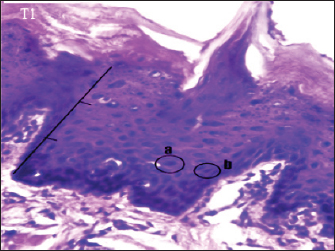

Fig. 3. Histopathological description of the rat tongue epithelium in the T1 group, microscope at ×400. (a) the ratio between the nucleus and the cytoplasm increases, with a hyperchromatic nucleus; (b) the shape of the nucleus showing anisonucleus.

The histopathology of the tongue epithelium of rats in the T1 group revealed dysplastic cells. Cell form and size variations (anisocytosis and pleomorphism) and irregular epithelial stratification due to nuclear shape and size differences. The ratio of nuclei to cytoplasm rises, and hyperchromatic nuclei are visible. Cell changes affect two-thirds of the thickness of the rat tongue epithelium. Therefore, this is classified as mild dysplasia (Fig. 3).

The T1 group had dysplastic alterations in the epithelium of the rat tongue as the (C+) group. This group exhibited mild dysplasia limited to one-third of the epithelium (basal and parabasal layers). According to Speight (2007), moderate dysplasia (grade II) is characterized by abnormal cell proliferation extending to the middle third of the epithelium, more severe cytological alterations than mild dysplasia, and the presence of hyperchromatic cells and prominent nuclei. Loss of basal polarity can be observed near the base of the epithelium, indicating tissue alterations.